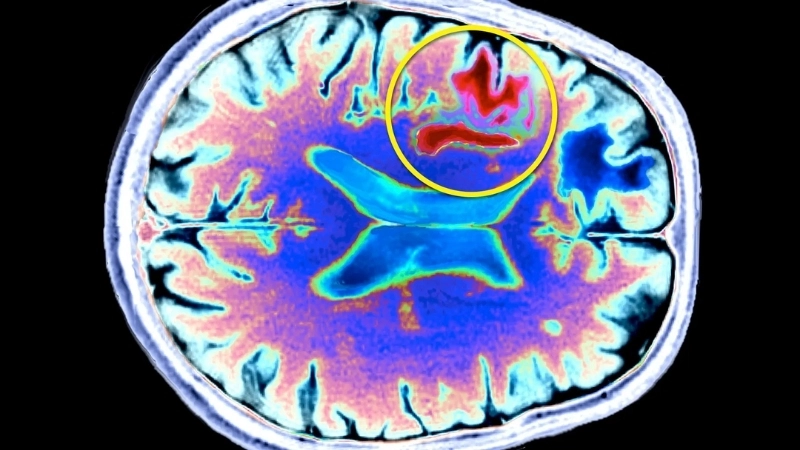

Image description of Progressive Multifocal Leukoencephalopathy (PML)

Progressive Multifocal Leukoencephalopathy (PML) is a rare, often serious viral disease that damages the brain’s white matter, leading to neurological complications. Early detection and medical management are crucial.